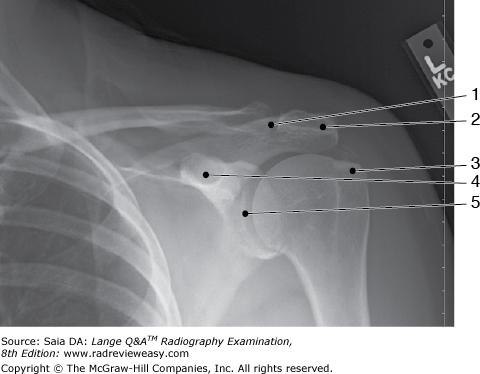

The structure labeled number 4 in Figure 2–41 is the

coracoid process

What projection was used to obtain the image seen in Figure 2–41?

AP, external rotation

The structure labeled number 5 in Figure 2–41 is the

glenohumeral joint